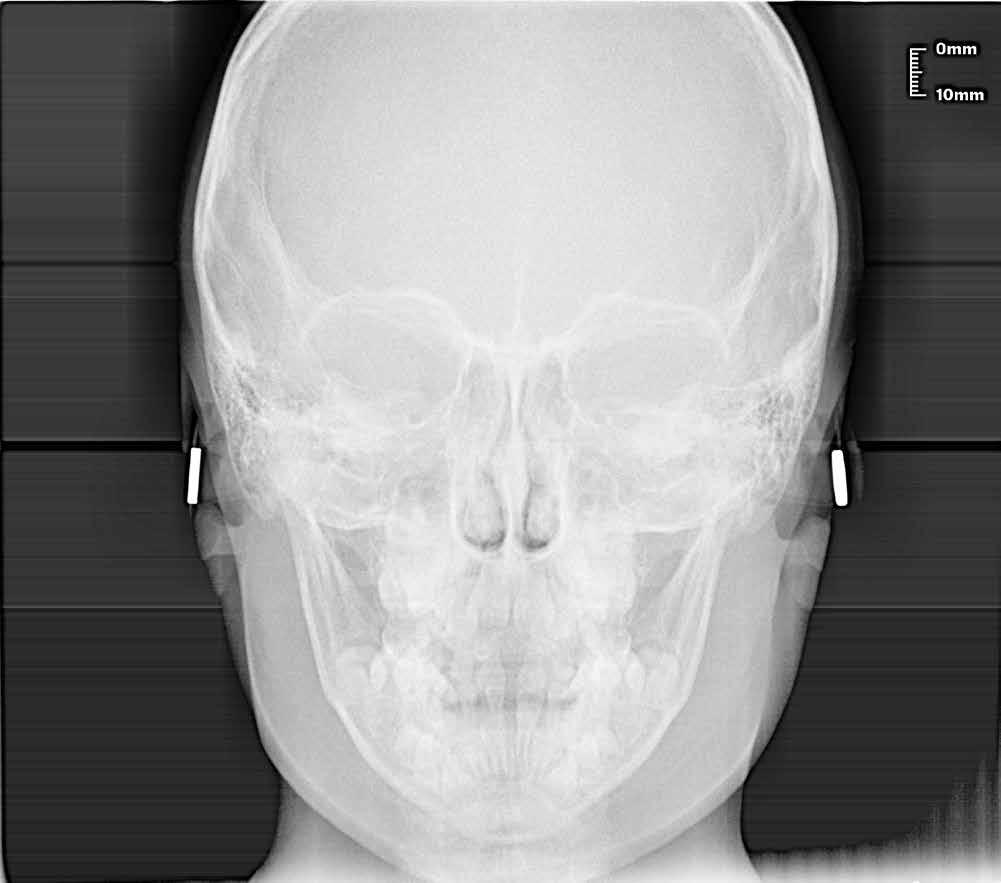

Alla risoluzione della malocclusione scheletrica e dentale si associa un netto recupero della postura con conseguente miglioramento della curva cervicale, come è possibile verificare nella teleradiografia finale.

47 46 ESTETICA FUNZIONE POSTURA Valori cefalometrici a 10 anni : ANB ANB 2.70 Posizione del Mascellare SNA 78,70 Posizione della Mandibola SNB 76.0 Angolo Articolare SArGo 142,76 Angolo Goniaco ArGoMe 125,73 Angolo incisivo inf^Corpo madibolare IiMand 92,00 Angolo incisivo Sup^Base Cranica Ant. IsCran 96,00 Angolo Interincisivo II 130,0 53 _ Esame Cefalometrico a dieci anni. 54 _ Tabella dei valori cefalometrici a dieci anni. 55 _ Ortopantomografia di controllo a dieci anni. 56 _ Teleradiografia di controllo con evidente stabilità del caso dal punto di vista scheletrico/posturale.

> La documentazione a dieci anni mostra la stabilità del caso e

come l’occlusione, elastodonticamente individuata, costituisca anche la contenzione stessa. La paziente ha smesso di

Considerazioni

indossare l’apparecchio elastodontico dopo due anni e mezzo di terapia, conservando parametri occlusali e posturali in rapporto corretto tra loro.

Nel 2019 si è provveduto all’avulsione chirurgica degli elementi dentari 18, 28, 38 e 48.

62 _ Radiografia postero-anteriore iniziale.